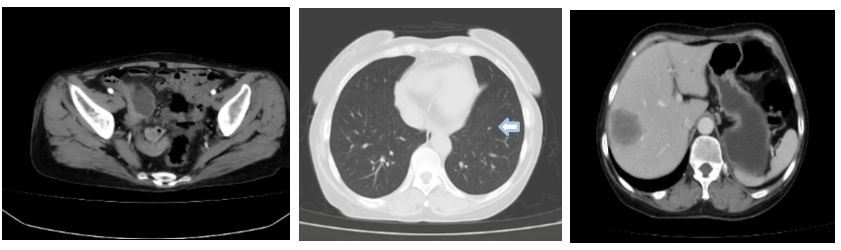

CT提示:肝内多发结节及肿块较前增大,左肺下叶前内基底段结节约0.7*0.6cm。

2024年6月26日复查胸腹盆C检查,提示肝内多发转移,大者径约4.3*3.6cm,较前增大;左肺下叶前内基底段结节,径约1.0cm,较前增大,新增右肺上叶前段两枚小结节,倾向MT。

2024年11月15日复查胸腹部CT检查,提示肝脏部分缺如,术区多发斑片状低密度影;腹腔肠管吻合口处线样致密影,符合术后改变,双肺多发结节(较大者0.8cm),考虑MT,较前略增大。

2025年3月12日复查CT提示肺部病灶增大,疗效评价为PD。

2025年6月5日复查CT提示双肺多发结节,较大者位于左肺下叶前内基底段,长径约2.2cm,考虑MT,较前不同程度增大。

2025年7月16日复查CT提示双肺多发结节,较大者位于左肺下叶前内基底段,长径约2.0cm,考虑MT,较前不同程度缩小。